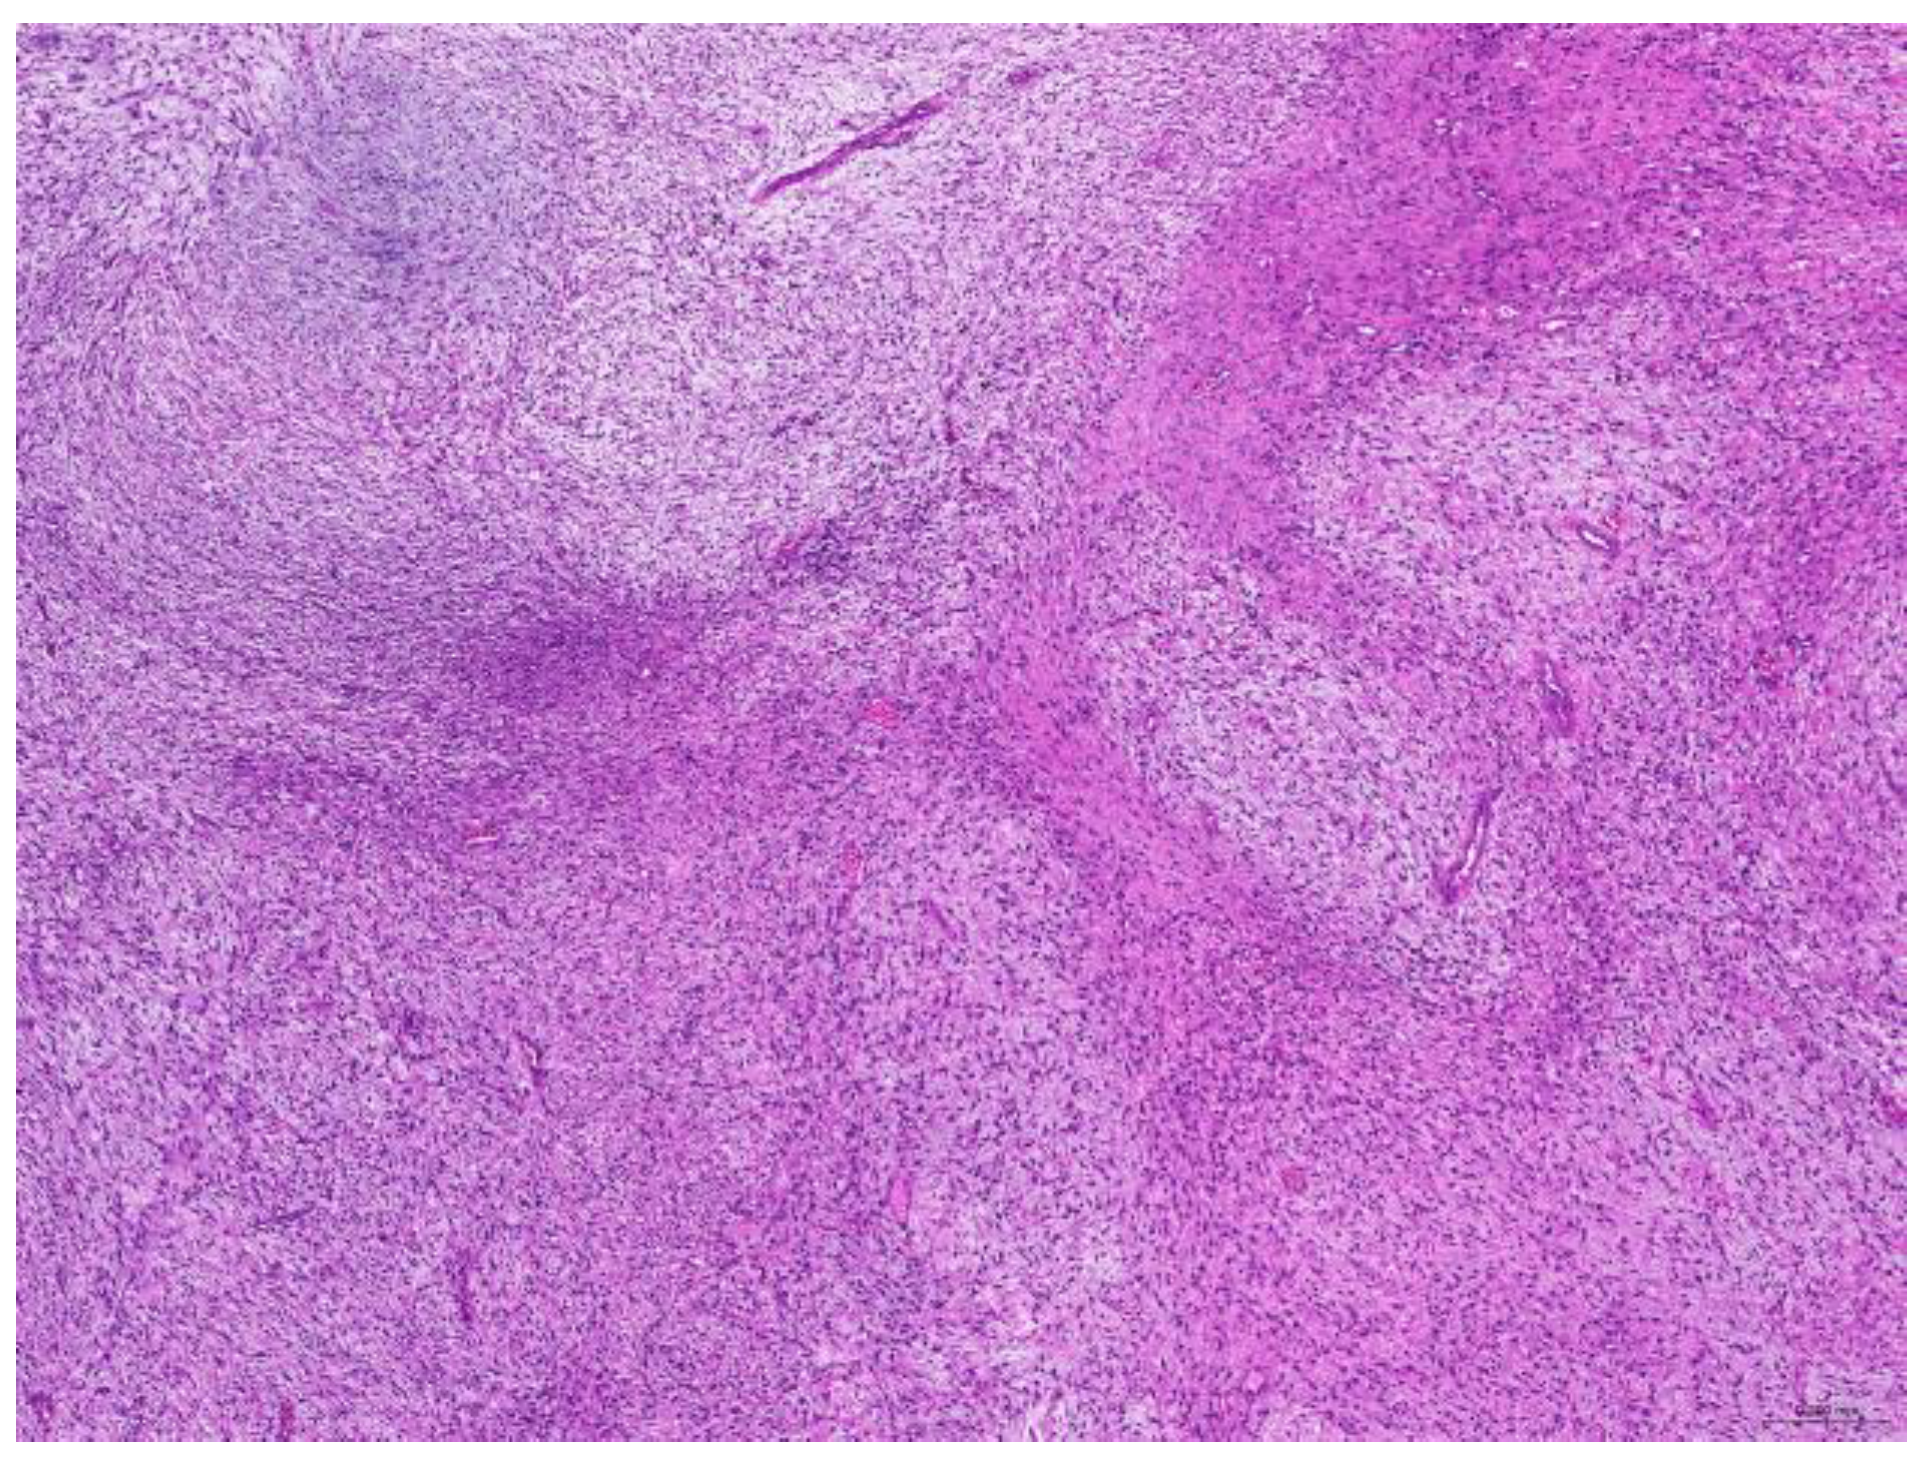

Of the 85 biopsy samples, the most commonly affected system was the integumentary system (48.2%, 41/85), followed by the reproductive system (42.4%, 36/85), the digestive system (8.2%, 7/85), and the urinary system (1.2%, 1/85) (Table 3). Of the 41 rabbits with an affected integumentary system, 39 had neoplastic and two had non-neoplastic disorders. The median age of these affected rabbits was 87 (12–149) months. There were 15 females and 26 males, with a female-to-male ratio of 0.54:1. The most common integumentary diagnosis was fibrosarcoma (29.3%, 12/41) (Figure 1), followed by trichoblastoma (19.5%, 8/41) (Figure 2), fibroma (9.8%, 4/41) (Figure 3), lipoma (7.3%, 3/41), mammary gland adenoma (7.3%, 3/41), and mammary gland adenocarcinoma (4.9%, 2/41) (Figure 4), among others. The median age of the rabbits with fibrosarcomas was 108 (54–126) months. Of the 12 cases with fibrosarcoma, 4 were females and 8 were males, with a female-to-male ratio of 0.5:1. The tumors were located on the neck, chest, abdomen, and extremities. The median age of the rabbits with fibromas was 101 (48–108) months. All four of these were males, with tumors exclusively located on the chest. Myxosarcoma was diagnosed in a 108-month-old male rabbit, with the tumor located on the left elbow (Figure 5).

Figure 2. Trichoblastoma. Neoplastic cells are arranged in trabeculae (scale bar = 500 µm). Hematoxylin and eosin staining.